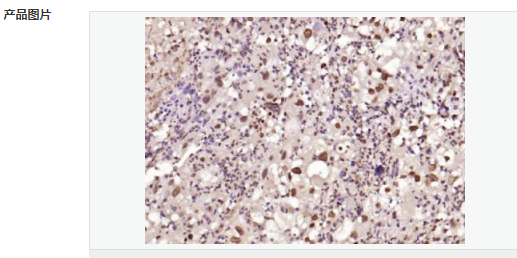

交叉反應(yīng):Human,Mouse,Rat(predicted:Dog,Pig,Rabbit,GuineaPig) 推薦應(yīng)用:IHC-P,IHC-F,ICC,IF,Flow-Cyt,ELISA

| 產(chǎn)品應(yīng)用 | ELISA=1:5000-10000 IHC-P=1:100-500 IHC-F=1:100-500 Flow-Cyt=1μg/Test ICC=1:100 IF=1:100-500 (石蠟切片需做抗原修復(fù)) not yet tested in other applications. optimal dilutions/concentrations should be determined by the end user. |